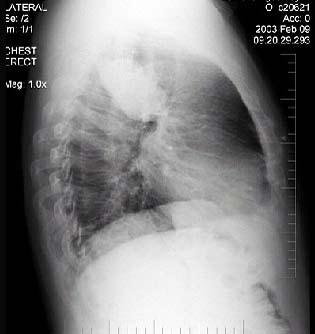

男性,70岁,因胸痛就诊,不咳嗽、发热,X线检查如图,最可能的诊断是 ( )A.左肺结核瘤B.左侧叶间积液C.左肺癌D.左肺炎性假瘤 ...

问题 男性,70岁,因胸痛就诊,不咳嗽、发热,X线检查如图,最可能的诊断是 ( )

选项 A.左肺结核瘤 B.左侧叶间积液 C.左肺癌 D.左肺炎性假瘤 E.支气管扩张

答案 C